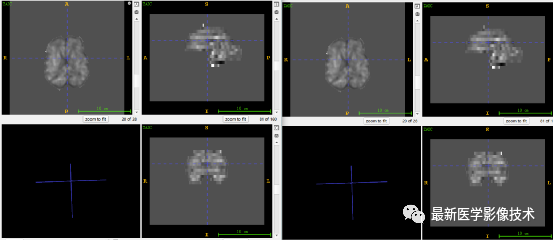

6、测试集分割结果

左图是金标准结果,右图是预测结果。